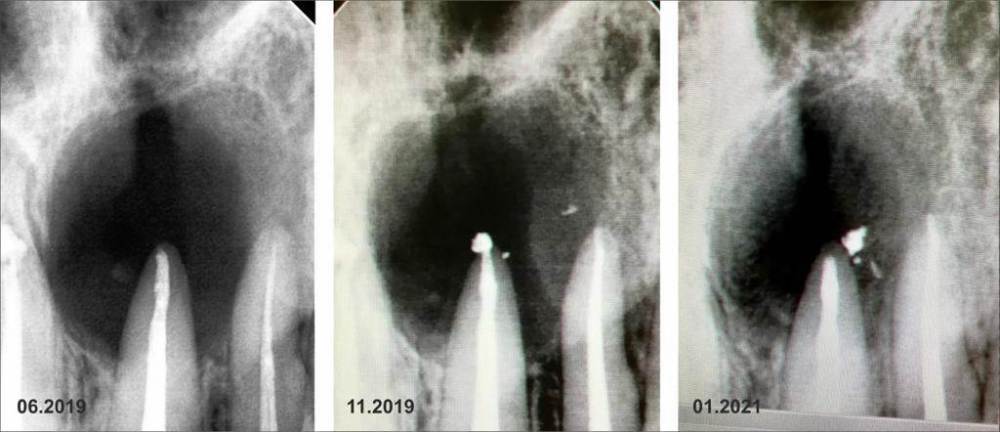

feGTX Опубликовано 15 июля, 2022 Поделиться Опубликовано 15 июля, 2022 (изменено) Здравствуйте. Очень нужна помощь стоматологов! В 2019 году обнаружил свищ над верхними передними зубами. Пошел к своему стоматологу, который начал следующее лечение: - нервы в зубах были удалены и пару дней я ходил с открытым каналом. Далее закладывался Метапекс, а потом постоянная пломба, но свищ не закрылся. 22 зуб также залечили. Были консультации и в других стоматологиях нашего маленького городка (КТ тогда тоже делалось), но в основном рекомендовали три зуба под удаление, закладывание искусственной кости, импланты или мосты на соседние зубы. Решили пробовать перелечивать со своим стоматологом. - 21 зуб снова вскрыли и несколько раз закладывали Кальцетин. Потом снова постоянная пломба. И свищ закрылся (это было осенью 2019 года). Далее делали несколько снимков - вроде медленно шло заживление. В сентябре 2021 года делал КТ нижней челюсти по другой проблеме, и захватилась верхняя челюсть - тоже были видны улучшения в сравнении с самой первой КТ. И вот на днях снова свищ на десне. Надавливаю под носом и выходит жидкость. Снимок сделали, но как-то коряво вышел он. Сделал также КТ. Снова всё плохо. Во вложении три старых снимка, один свежий, и несколько изображений с КТ. Если нужны еще какие-то срезы, то попробую сделать. Помогите пожалуйста. Изменено 15 июля, 2022 пользователем feGTX Ссылка на комментарий